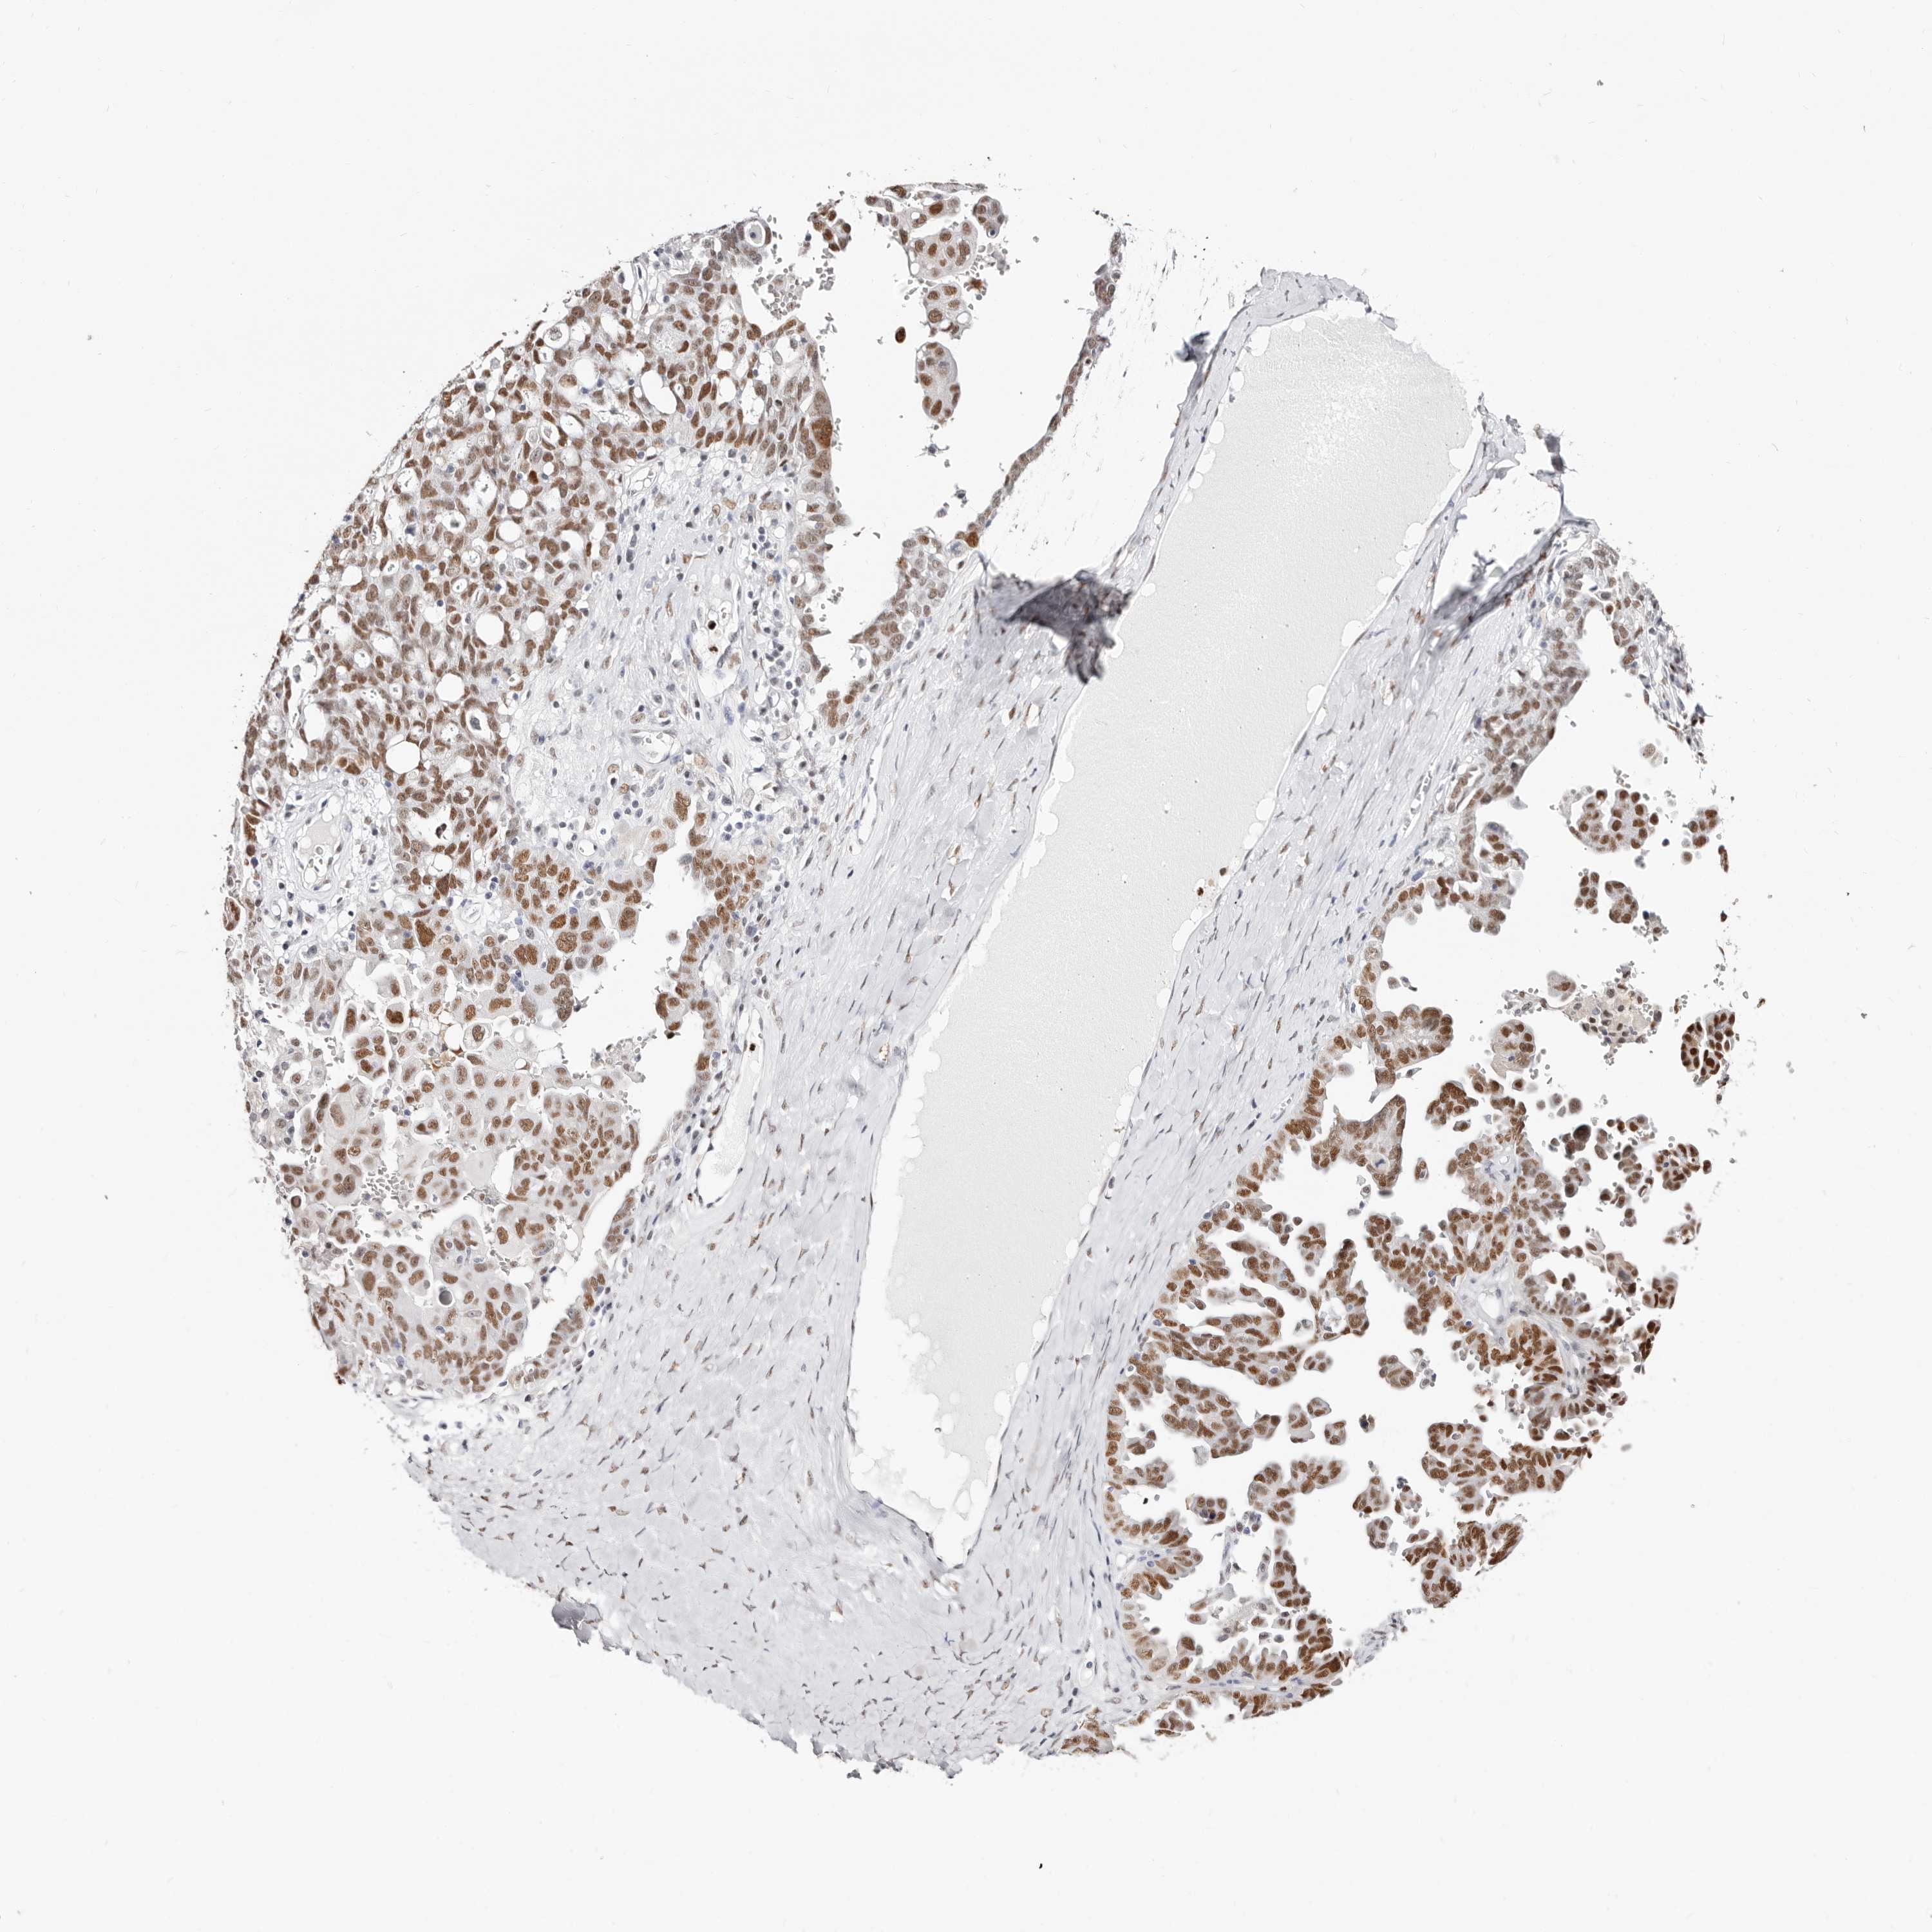

OVARIAN CANCER - Protein expressioni

A mouse-over function shows sample information and annotation data. Click on an image to view it in a full screen mode. Samples can be filtered based on level of antibody staining by selecting one or several of the following categories: high, medium, low and not detected. The assay and annotation is described here.

Note that samples used for immunohistochemistry by the Human Protein Atlas do not correspond to samples in the TCGA dataset.

Antibody stainingi

Antibody staining in the annotated cell types in the current human tissue is reported as not detected, low, medium, or high, based on conventional immunohistochemistry profiling in selected tissues. This score is based on the combination of the staining intensity and fraction of stained cells.

Each image is clickable and will lead to virtual microscopy that enables deeper exploration of all samples and also displays staining intensity scores, fraction scores and subcellular localization as well as patient and tissue information for each sample.

Antibody HPA029480

Antibody HPA029481

Carcinoma, endometroid